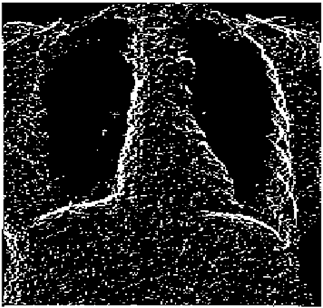

Table 5. X-ray Images.

X-ray 1X-ray 2X-ray 3X-ray 4X-ray 5

Mathematics 10 02421 i004 Mathematics 10 02421 i005 Mathematics 10 02421 i006 Mathematics 10 02421 i007 Mathematics 10 02421 i008

For the purpose of simulation, we consider two sets of images: (1) three images from MATLAB repository (Table 4) and (2) five X-ray images available online (Table 5).

Table 10 shows the following:

• In all cases, the Canny edge detector detects more edge pixels than both fuzzy compositions.

• As the level of noise increases, Canny and standard composition become adversely affected by the noise, and still more edges are detected by Canny; however, most of the detected edges by Canny are misdetections due to the impact of noise. As is obvious from this table, the smooth composition provides a better image with reduced noise density.

• In all cases, the PFOM value for the smooth composition is always greater than the PFOM value for the standard composition, according to Table 6.